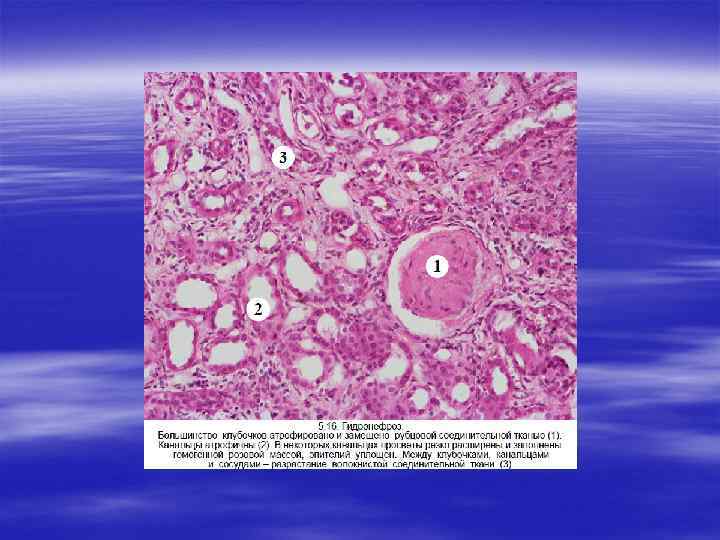

ГИДРОНЕФРОЗ § Гидронефроз представляет собой дилатацию почечной лоханки и чашечек, сопровождающуюся атрофией паренхимы. Основная причина гидронефроза — это обструкция мочевыводящих путей на любом уровне от уретры до почечной лоханки. Обструкция может быть внезапной или развиваться исподволь, врожденной или приобретенной, полной или частичной.

§ Основными причинами врожденного гидронефроза являются: § 1) атрезия уретры, § 2) опущение (птоз) почек, § 3) сдавление мочеточников аберрантной почечной артерией.

§ К развитию приобретенной обструкции мочевыводящих путей ведут: 1) камни, некротизированные почечные сосочки; § 2) различ ные опухоли: гипертрофия простаты, рак простаты, опухоли мочевого пузыря (папиллома, рак), ретроперитонеальная лимфома, рак тела матки, шейки матки; § 3) воспалительные процессы: простатиты, уретриты, уретериты, ретроперитонеальный фиброз; § 4) нейрогенные факторы: повреждение спинного мозга с последую щим развитием паралича мочевого пузыря; § 5) нормальная беременность, при которой развивается легкая и обратимая форма гидронефроза.

ВТОРИЧНЫЕ НЕФРОСКЛЕРОЗЫ § Поражение почек любой этиологии в итоге ведет к почечной недостаточности, структурной основой которой является нефросклероз. Нефросклероз представляет собой патологический про цесс, сопровождающийся разрастанием фиброзной ткани с уплот нением и сморщиванием почек. Поверхность почек приобретает зернистый или бугристый характер. В зависимости от причин выделяют две основные группы нефросклероза: первичное и вто ричное сморщивание почек.